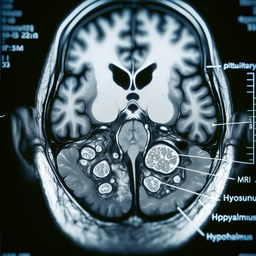

### Основні аспекти МРТ гіпофіза:

1. **Призначення**:

- Виявлення аденом (доброякісних пухлин).

- Оцінка інших патологій, таких як порушення гормонального балансу.

- Дослідження структури гіпофіза при підозрі на інші новоутворення чи зміни.

4. **Переваги**:

- Висока точність і деталізація зображень.

- Відсутність іонізуючого випромінювання.